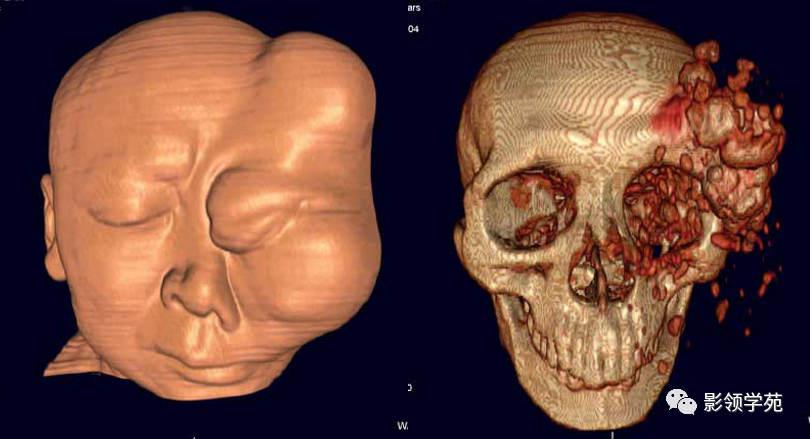

CT诊断:甲状腺癌双肺多发转移